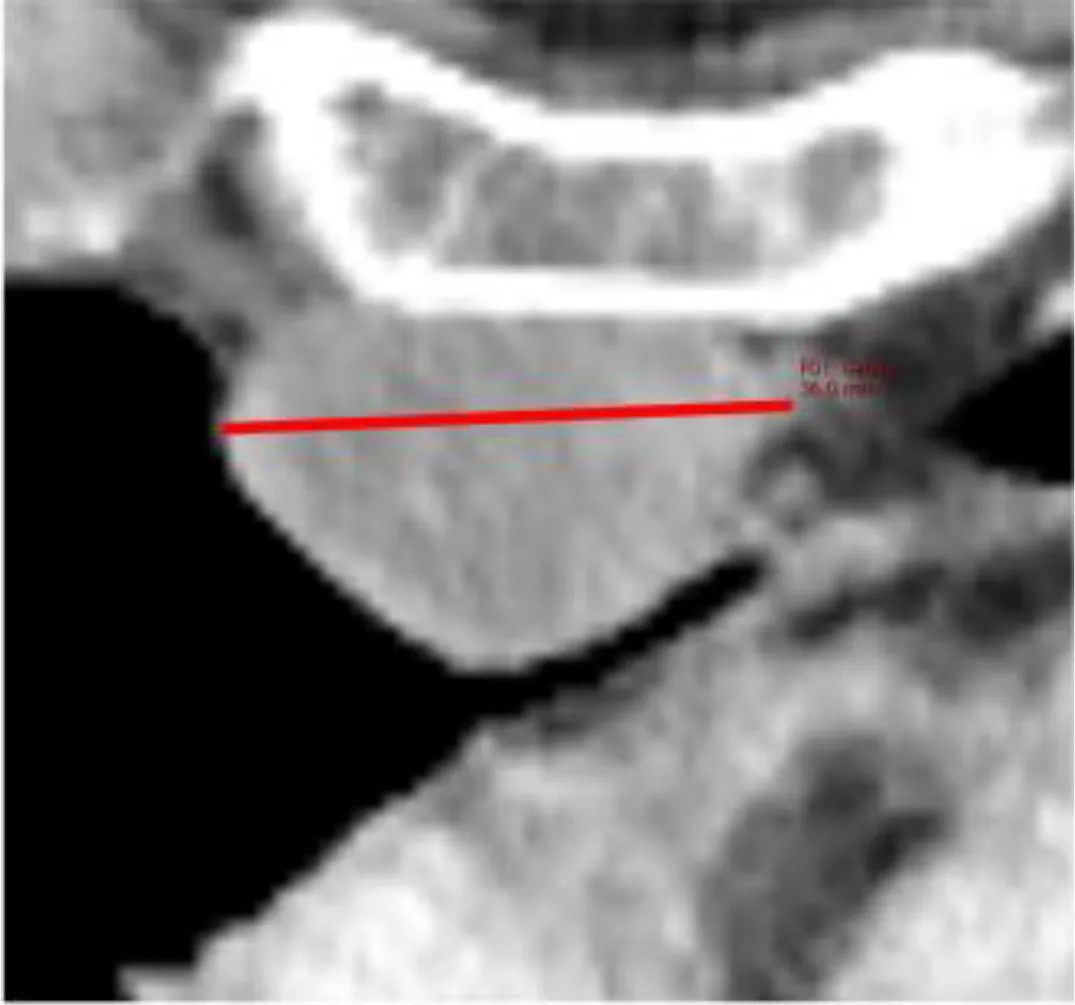

The reference value for correlation analysis was set to TBMTV. The correlation of total TBRECIL with total TBMTV was ρ=0.744 (0.546-0.863, p<0.001), and total TBLugano with total TBMTV ρ=0.741 (0.542-0.862, p<0.001). The correlation of TBRECIL or TBLugano with TBMTV was the lowest for extranodal disease. The results are illustrated in Figure 2. TBRECIL and TBLugano displayed a strong positive correlation for total (ρ=0.983 [0.967-0.992], p<0.001), nodal (ρ=0.938 [0.880-0.968], p<0.001) and extranodal TB (ρ=0.896 [0.803-0.947], p<0.001). Patient examples for the largest deviations are depicted in Figure 3.

Figure 3

Despite the numerically strong correlations among morphologic and metabolic methods, we identified several statistical outliers. We identified two patterns that led to the divergence in these patients: (1) disseminated lesions in extranodal disease, which led to underestimation by TBRECIL or TBLugano, and (2) metabolically inactive disease with large residual masses (e.g. after bridging therapy) that led to overestimation by TBRECIL or TBLugano when compared with TBMTV. These potential reasons of divergence among TB metrics should be considered as potential sources of bias when comparing results from different trials.